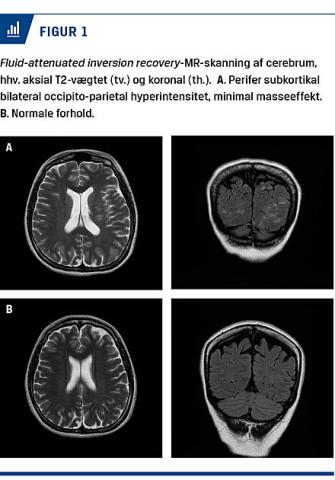

Fjorten dage post partum blev hun indlagt akut på en neurologisk afdeling efter tre dage varende voldsom hovedpine, kvalme, opkastninger, tiltagende dårligt syn og trykken for brystet. BT blev målt til 200/130 mmHg. EKG’et viste nu sinustakykardi med venstresidig hypertrofi og belastning. Der blev påbegyndt behandling med metoprolol. En oftalmologisk undersøgelse viste fundus hypertonicus grad IV. Kvinden blev overflyttet til et kardiologisk afsnit med diagnosen hypertensiv krise. Man indstillede behandlingen med metoprolol og gav i stedet labetalol med senere tillæg af amlodipin under tæt kontrol af BT. Kvinden var under indlæggelsen cerebralt påvirket i form af hukommelsesbesvær. En akut foretaget CT af cerebrum viste normale forhold, men på en MR-skanning var der tegn på posterior reversibel encefalopati som vist på Figur 1A.

Den mest sandsynlige forklaring på det brogede og alvorlige symptombillede er posterior reversibel encefalopati-syndrom (PRES), et neurotoksisk syndrom, som er karakteriseret ved cerebrale ødemer, oftest i parietal- og occipitalregionerne. Diagnosen stilles ud fra symptomerne og MR-skanning. Diagnostikken er ikke enkel, og der er mange faldgruber. Patofysiologien er ukendt, men man mener, at de cerebrale ødemer opstår pga. hyperperfusion, som overstiger autoreguleringen [2].